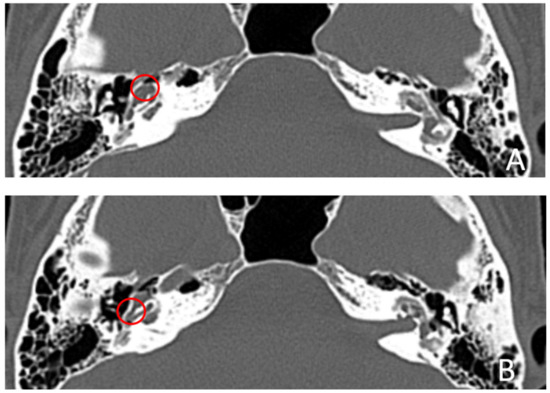

Patient #5, affected by otosclerosis: She developed mild CHL on the right ear at the age of 29 and then mild CHL on the left side at the age of 36. On the right she progressed to moderate MHL, but on the left she progressed to severe SNHL. On CT and MR images (Figure 9 and Figure 10), the otosclerotic lesions are well visible bilaterally, but only the right ear was included in the study because a cavity around the cochlea, communicating with the perilymph, was present only on the right side. The patient received a left cochlear implant 10 years after diagnosis.

Figure 9. CT images of patient #5 with otosclerosis. (A,B), axial plane. The cavity around the cochlea is only visible on the right side (the circles indicate the contact of the osteorarefation with the cochlea), instead there is only an otosclerotic process without cavity on the left side.

Figure 10. MR images of patient #5 with otosclerosis. MR cisternography. (A,B), axial plane. Note the presence of fluid signal in the newly formed cavity on the right side only (white asterisks).